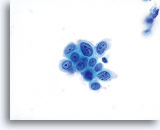

对于 ThinPrep® 涂片检测,HSIL 的诊断标准如下: 单个细胞(HSIL 最重要的标准)是不对称三维胞核结构异型的表现。为掌握 HSIL 诊断,必须对此概念有明确的理解。不良胞核的结构将发生异型变化;对于这些胞核而言,只有对单个细胞的焦距进行上下控制,才可对这些胞核做出彻底的诊断。此概念是最难以在书本图片(二维页面)上展示的;然而,这却是最为重要的。

试想想对一个微缩的花椰菜、握紧的拳头、棒球或扁桃腺的焦距进行上下对焦。葡萄干的表面看起来像什么?正常胞核的形状相对较圆或呈椭圆形,并且其表面也是平滑的。不良细胞将具有凸起、凹陷、褶皱、裂纹和奇怪的隆起。这些非常明显的异型性是异生性(特别是 HSIL)的基本特征;而由于传统的细胞涂片在固定和染色过程中会存在各种干扰物质,上述的细节往往会在传统的细胞涂片丢失 , 这样令传统涂片的诊断能力造成限制。

这些三维细胞结构的异型性可与简单的“不规则细胞核轮廓”区别开来;在 ThinPrep® 玻片上,这些将是良性细胞的一种特征表现。由于是二维的, 由于是二维的,当检查员在显微镜下上下对焦时,这些“褶皱”像裂缝或山脉般难以在胞核中心被追踪,这样会为无经验者做成相类似的假像。

在玻片上,并不是每个不良细胞都会呈现出这些三维结构的异型性;但是,在这些玻片上,这些异型性至少会在一些细胞中较为明显。显然,染色质量直接关系到是否能够看到胞核“内部”。(与传统的巴氏涂片相比,所有的 ThinPrep® 涂片检测都使得细胞变化更为明显;但如果对反应物进行过度染色,或有轻微腐败,都将对这种最为重要的评估标准造成直接影响)。此外,与细胞凹陷或简单的褶皱(会达到胞核的全部宽度,具有“相似本体”,并会造成一定的难度)相比,这些三维结构的缺陷应该是不对称的。由于这些胞核的三维异型性能够得到放大,因此能够为 HSIL 诊断提供依据。